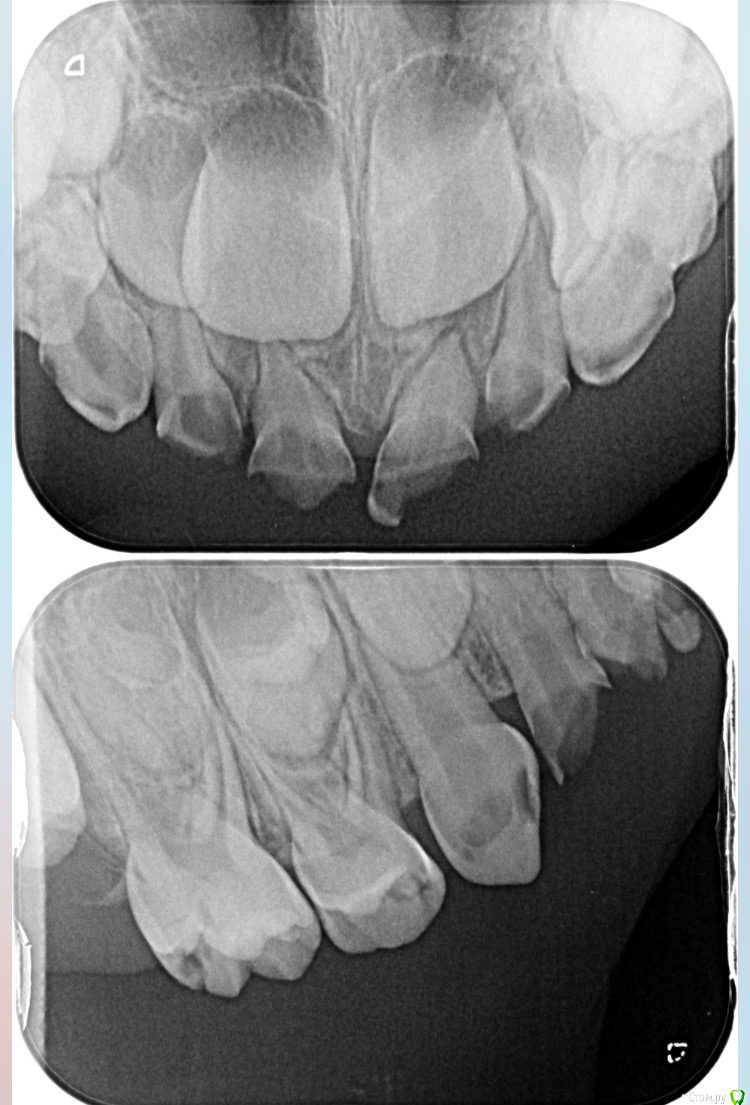

DAV86.06 Опубликовано 2 октября, 2017 Поделиться Опубликовано 2 октября, 2017 (изменено) Добрый вечер! Подскажите пожалуйста. Ребёнку 4года на жевательные зубки нижние предлагаютпоставить коронки. На сколько это актуально в нашем случае или можно обойтись пломбой? Изменено 2 октября, 2017 пользователем DAV86.06 1 Ссылка на комментарий

DAV86.06 Опубликовано 2 октября, 2017 Автор Поделиться Опубликовано 2 октября, 2017 Передние верхние зубы предлагают удалить тк лечить их смысла нет. И ещё нам насчитали 8 пульпитов♀ Ссылка на комментарий

ЕленаВалерьевна Опубликовано 2 октября, 2017 Поделиться Опубликовано 2 октября, 2017 с короночками будет надежнее, про пульпиты согласна с вашим доктором. по поводу передних зубов точно не могу сказать, только по снимку сложно ориентироваться, возможно и полечить получится. 1 Ссылка на комментарий